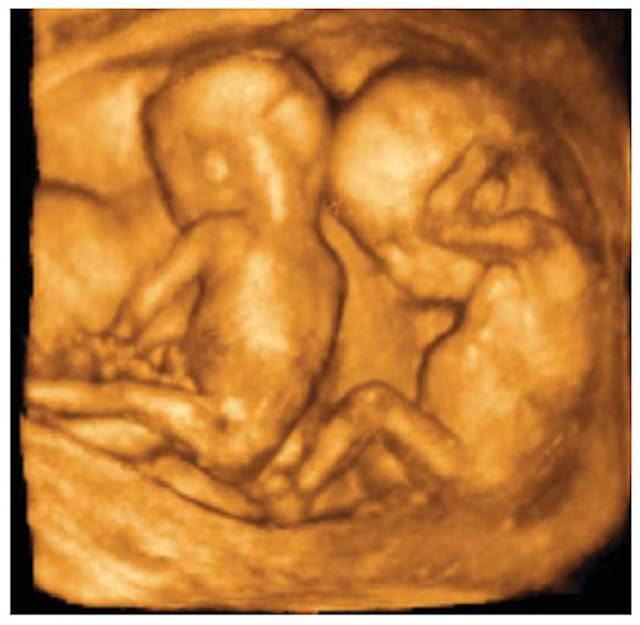

Watson stunned fans by putting the football under his shirt mimicking a pregnant belly and holding up seven fingers. Watson and his wife, Kirsten, have five children, so people weren’t sure what to make of the additional two fingers. Sure enough, Watson confirmed after the game that his wife Kirsten is 13 weeks pregnant with twins.

Watson has been outspoken about his pro-life beliefs and has publicly donated to pro-life causes. Earlier this year, the Watson family donated ultrasound machines to crisis pregnancy centers. Watson said the ultrasound machines “allow expecting mothers and fathers…to see the precious life God has given them reminding them of its dignity, beauty and value.”